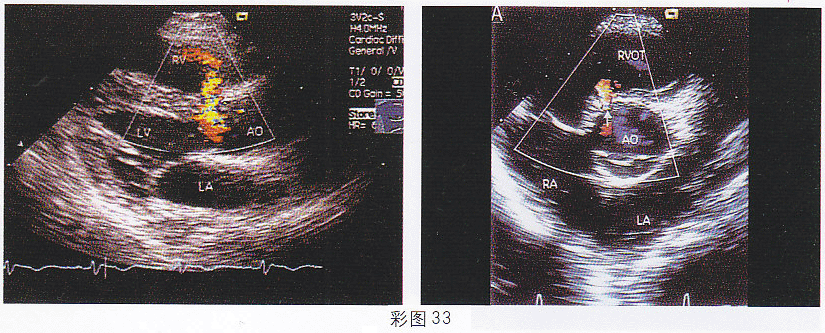

3.患兒,1歲,男,體檢發現胸骨左緣全收縮期雜音,超聲檢查如圖(彩圖33)所示。該圖所示的室間隔缺損屬于哪型

正確答案:A 解題思路:室間隔膜部缺口處探及過隔血流信號。